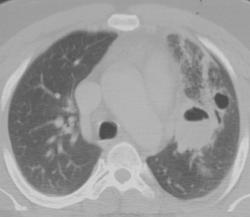

Бронхиальная атрезия

- в результате облитерации проксимального отдела сегментарного бронха (верхней доли), реже -долевой или субсегментарный бронх

• локальное вздутие пораженного сегмента

• бронхи дистальнее стеноза наполняются слизью - формируется бронхоцеле (мукоцеле)

• у новорожденных - вид кисты, заполненной жидкостью

• «воздушные ловушки» в результате гиперинфляции вокруг расширенных бронхов

• малочисленность сосудов в зоне поражения

• клинически - чаще бессимптомны

Бронхиальная атрезия.

Бронхиальная атрезия.

Бронхиальная атрезия.

Бронхиальная атрезия

Бронхоцеле

Атрезия бронха